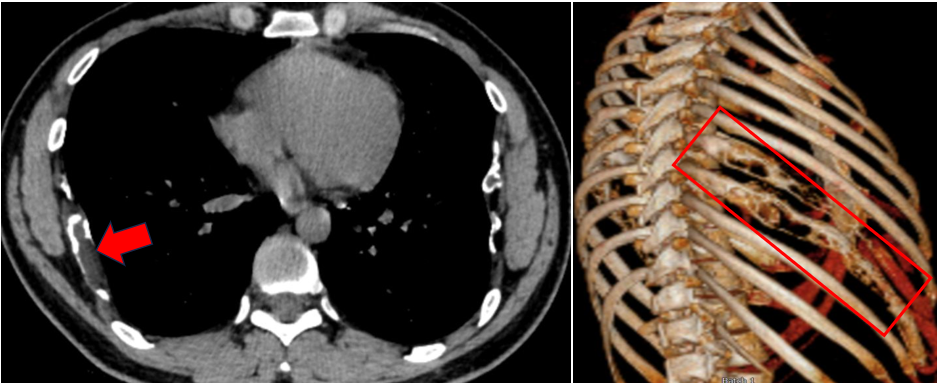

术前胸部CT及肋骨三维重建

近期,我院收治1例中年男性患者,主因“发现双侧肋骨肿物伴右侧胸部疼痛半年”入住胸外科。 胸部CT检查提示:右侧第7、8及左侧第6、7肋骨骨质膨胀性破坏,形态不规则,考虑骨纤维结构不良可能。结合患者病情及病灶范围,考虑患者当前症状以右侧胸痛不适为主,影像学表现虽考虑良性病变,但病灶存在进一步进展风险,遂优先行胸腔镜下右侧胸腔第7、8肋骨肿物切除术,手术顺利,完整切除病变肋骨及相邻组织。术后病理:右侧第7/8肋纤维结构不良。术后恢复良好,顺利出院。